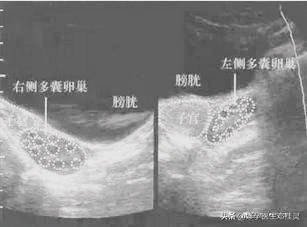

4.右侧卵巢大小约3.5×2.9cm,最大乱拍大小约0.9×0.9cm。左侧卵巢大小约3.2×2.4cm,最大卵泡大小约0.7×0.7cm .

5.双侧卵巢形态饱满,每平面看探及约10+个小卵泡,髓质回声略强。

多囊卵巢综合征患者的B超检查单